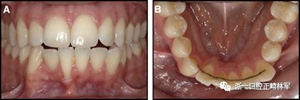

臨床檢查顯示固定保持器完好,弓絲沒有斷裂(圖13)。在下頜右側中切牙唇側和鄰近側切牙的舌側注意到有牙齦退縮。這些牙齒在退縮方向上存在顯著的扭矩差異。下頜的左側尖牙頰側錯位,而右側尖牙舌側傾斜。三維射線照片證實了下頜右側尖牙面側牙槽骨喪失,右側中切牙的喪失程度較輕。右側側切牙根也從舌側骨面上扭轉出來(圖14)。

正畸文獻閱讀--固定舌側保持器作用下意外的牙齒移動

圖13.粘合到尖牙和切牙上的柔性螺旋弓絲保持器,伴有牙齦退縮和附著喪失,中切牙之間嚴重的扭矩差異以及兩顆尖牙的橫向移動和扭矩。牙周問題和牙齒移動的嚴重程度均為牙周正畸聯合治療的指征:A,正面視圖; B,咬合面視圖。